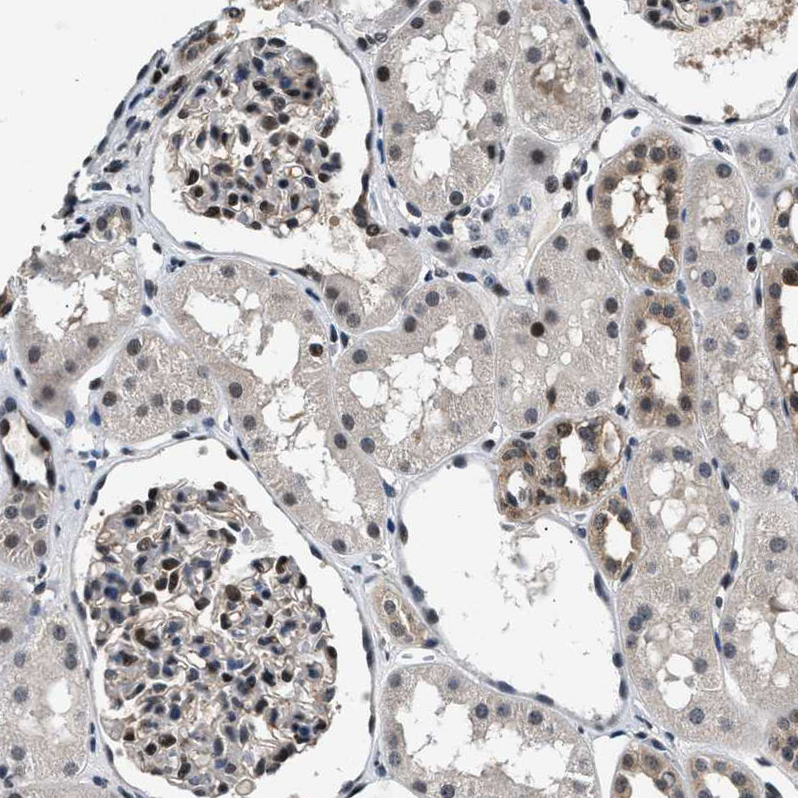

Immunohistochemical staining of human cerebellum shows moderate nuclear positivity in Purkinje cells.